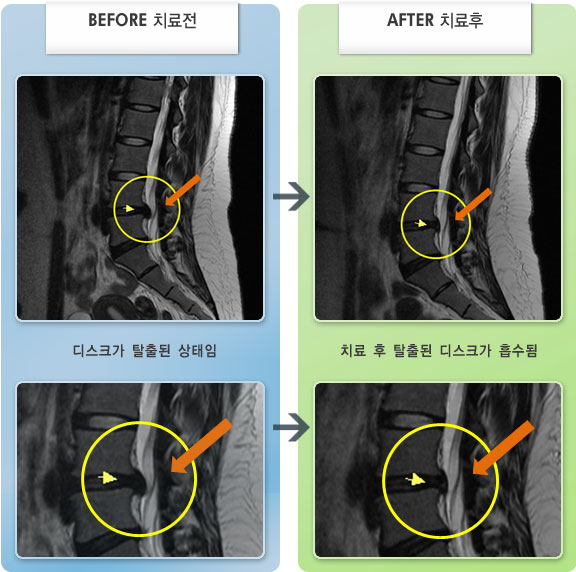

MRI 치료사례

허리 통증과 우측 엉치에서 발끝 저림 증상